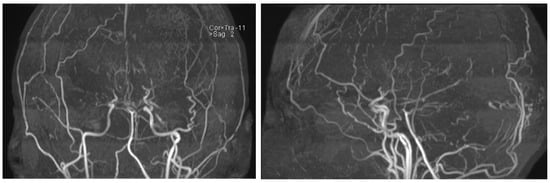

The first description of this condition dates back to 1957, when it was termed “hypoplasia of the bilateral internal carotid arteries”. Following the progressive narrowing of blood vessels of the anterior circulation, a dense collateral network of new vessels develops near the carotid apex, the cortical surface of the cerebral hemispheres, the leptomeninges, and around branches of the external carotid artery, supplying the dura mater and the skull base. Rarely, such a network may form among the vessels of the posterior circulation, namely the basilar artery and posterior cerebral arteries. The characteristic appearance of those newly formed and dilated vessels on conventional angiography was described as “hazy, like a puff of cigarette smoke” (Figure 1), which in Japanese translates to moyamoya [1,2].

Figure 1. Angiographic findings in moyamoya [1].

Figure 4. MRI time-of-flight (TOF) angiography showing significantly diminished blood flow in the anterior circulation and the development of collateral blood vessels.